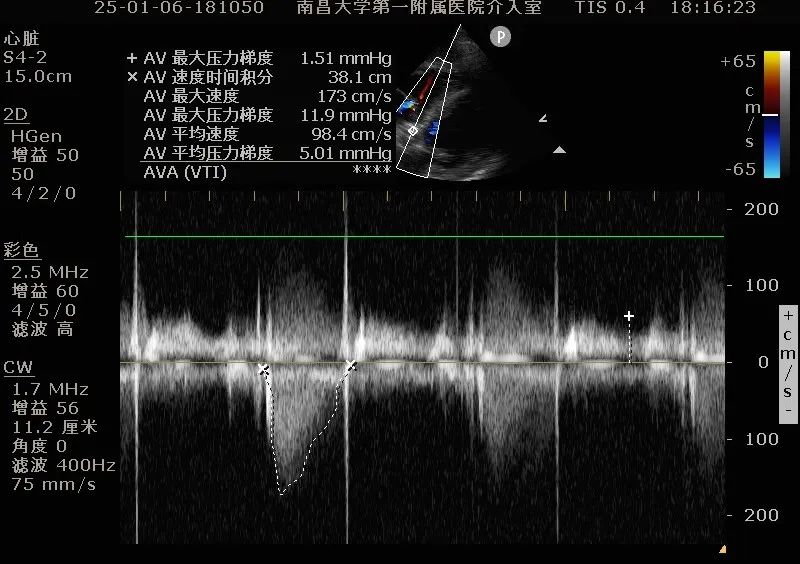

复查造影提示瓣膜固定良好,形态尚可,未见明显反流;复查超声提示瓣膜功能正常,平均跨瓣压差下降至5.01mmHg,未见明显瓣周漏;最后退出鞘管,缝合血管。